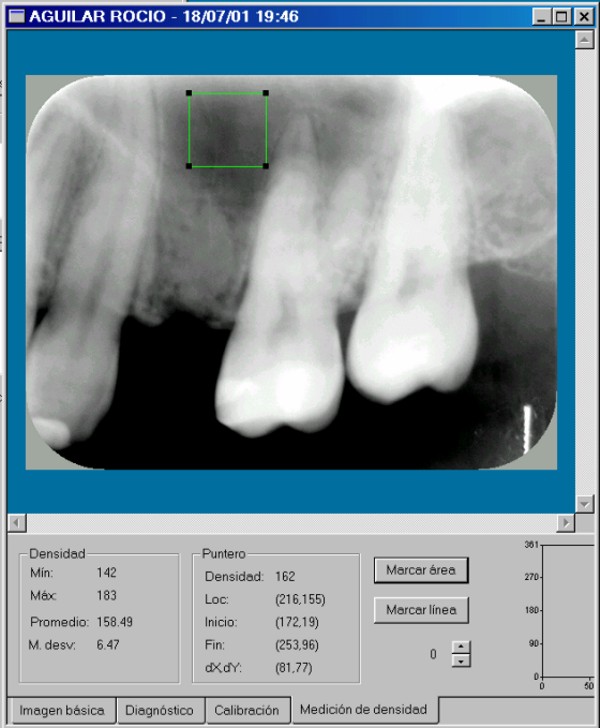

Hubiera sido necesaria la comparación osteodensitométrica entre la zona a implantar y otras zonas maxilares.(DIAPO 8-9-10)

DENSIDAD PROMEDIO:194.87 DENSIDAD PROMEDIO:158.49

DIAPO 8 DIAPO 9

DENSIDAD PROMEDIO:168.5

REF 1